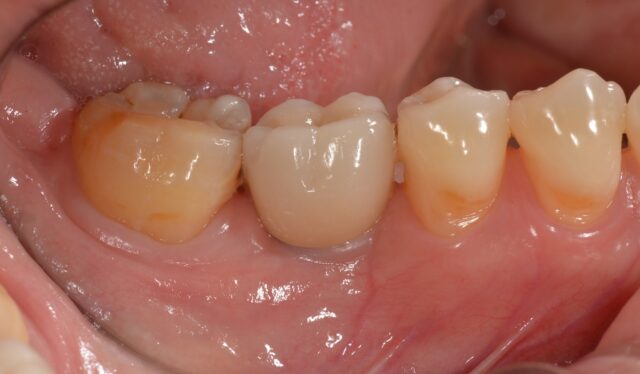

Before

| 主訴 | 歯冠破折 |

| 年齢・性別 | 8歳 男子 |

| 治療期間・回数 | 複数回 |

| 治療方法 | 見えていた歯髄の表層をとり(断髄し)、歯髄の傷が治りやすい薬で傷口を保護しました。その後、折れた破折片を、修復材にてもとの歯に接着しました。 |

| 費用 | 保険適用 |

| デメリット・注意点 | 定期的なレントゲンでのチェックが必要 |